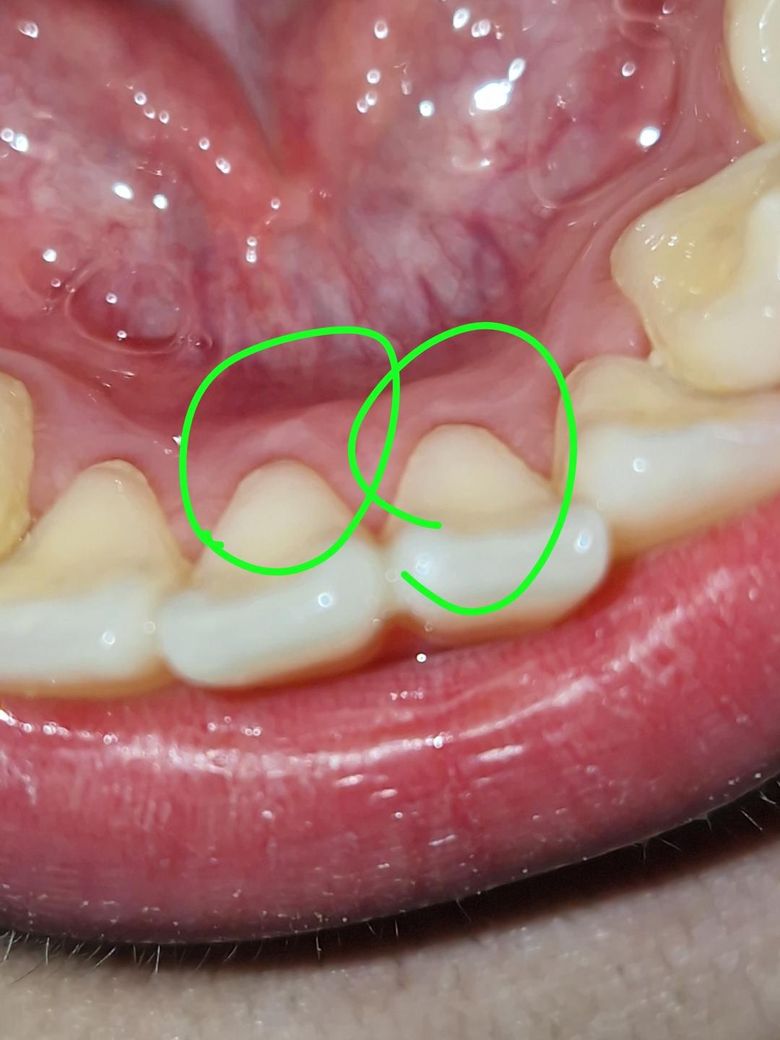

앞니 뒤 하얀색이 있는데 염증인가요?

앞니 뒤 잇몸인데 저렇게 하얗게 꽤 오래전부터 저 상태였어요. 피곤할때 조금 따끔? 한거 외에불편한 건 없는데, 혹시 염증일 수 있나요? 뭣때문에 저렇게 하얗게 나타나는지 궁금합니다

• 1번 째 사진

사진으로 봤을 경우에 하얀색으로 보이는 부위는 염증은 아닌 것으로 보입니다. 잇몸이 혈액이 적게 돌거나 하는 부분은 하얗게 볼 수 있습니다. 크게 문제가 되진 않을 것으로 생각되나 된다면 치과에서 진료를 받아보세요.

가벼운 염증으로 인해 잇몸에 하얗게 나타날 수 있습니다. 초기에는 증상이 미미하고, 따끔거리는 느낌이 있을 수 있습니다. 염증이 심해지면 붓기나 출혈이 발생할 수 있습니다.

따라서 초기에 치과에 방문하여 상태를 확인하고, 스케일링 및 검진을받아 관리하길 권합니다.